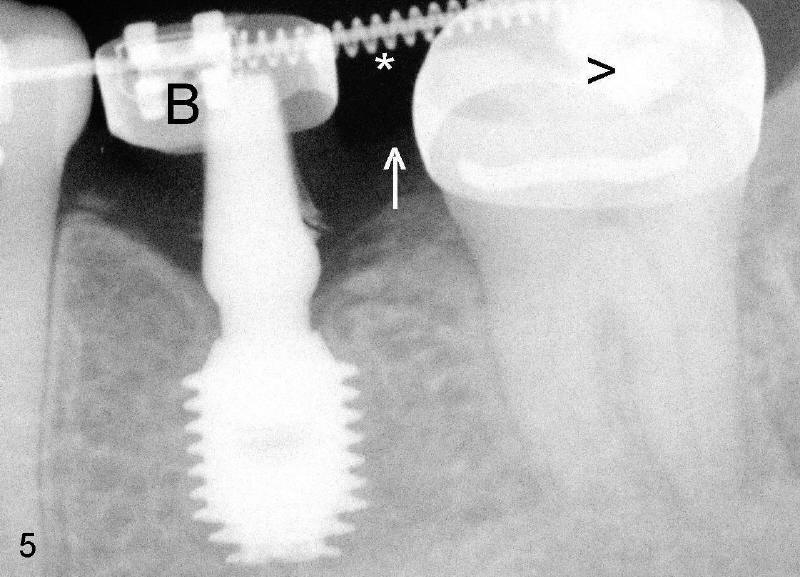

A premolar band (B in Fig.5) was cemented to the temporary crown of #19. In another two months, the tooth #18 was pushed to desired position (arrowhead) under the tension of open coil spring (*). The mesial crest height of #18 was increased during uprighting (arrow, as compared to Fig.3). Return to main article